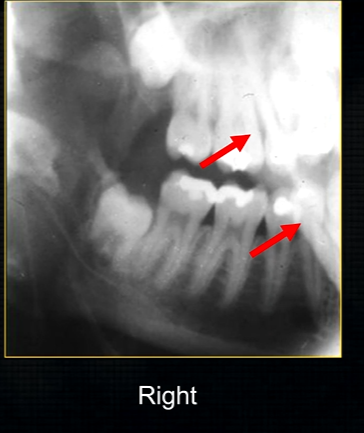

periapical radiograph → posterior maxilla

radiolucent maxillary sinus and radiopaque floor

radiopaque shadow cast by zygoma, hollowed out by maxillary sinus

lower end of the dense, zygomatic bone

posterior aspect of the maxilla - smooth round tuberosity